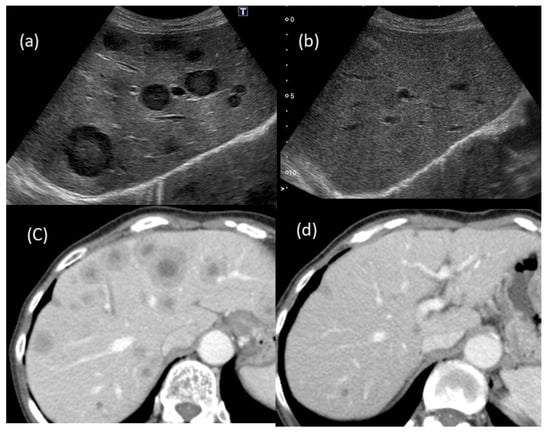

Around one month before her visit, she had developed a low-grade fever for a few days; however, no other remarkable episodes were experienced, and she recovered without receiving any new drugs. However, US revealed multiple liver masses with a maximum size of 33 mm, and the tumors had thick hypoechoic areas (halo sign) at their margins (Figure 1).

Figure 1. Abdominal ultrasonography (US). Multiple masses with the hypoechoic halo sign at their margins were detected. Some typical tumors with the hypoechoic halo sign are shown with arrows.

Figure 7. Changes in the US and CT findings: multiple tumors that had been suggested to be metastatic tumors (a,b) were barely detected after two months of observation; (a,b) US findings; (c,d) CT findings.

Despite the presence of findings suggestive of metastatic tumors (Figure 1 and Figure 2), we assessed several different types of clinical data available, such as different imaging techniques, and ultimately concluded that the tumors were benign. Thus, it is quite important to make a diagnosis by combining various imaging findings and considering the patient’s background and clinical course.